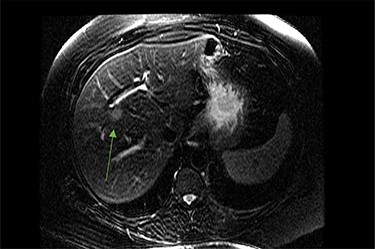

MRI image again demonstrating segment 5 metastatic lesion in close proximity to portal vein.

On assessment, the patient denied any symptoms related to her neuroendocrine tumor, including flushing, increased sweating, increased heart rate, wheezing, shortness of breath, diarrhea, weight loss or appetite changes. The only significant family history was a paternal and maternal grandfather with colon cancer. Imaging results were significant for computed tomography (CT) of chest demonstrating very small, but multiple, pulmonary nodules. A CT abdomen and pelvis demonstrated the known neuroendocrine tumor near the ileocecal valve (Fig. 1) as well as two poorly visualized liver lesions (Figs 2–4). The magnetic resonance imaging (MRI) demonstrated two separate one-centimeter lesions in segment 5 and 7 of the liver (Figs 5 and 6). The portal vein lacked normal left and right bifurcation; there was a circumferential right portal vein, which coursed anteriorly and superiorly and ultimately to the left lobe of the liver.